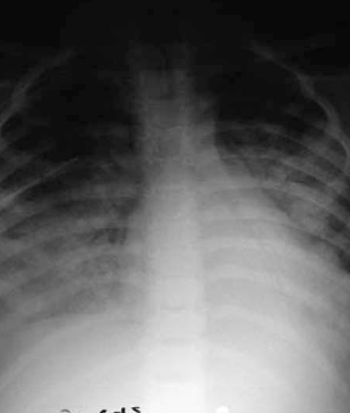

Se inicia oxigenoterapia de alto flujo (OAF) con rápido escalamiento a ventilación invasiva por gravedad clínica con compromiso del estatus neurológico y respiratorio, evolucionando al síndrome de dificultad respiratoria (SDRA) (Figura 2).

En una serie publicada de 11 pacientes entre 5 meses y 13 años, con LH y fallo multiorgánico (FOMS)9, el compromiso respiratorio estaba presente en siete pacientes con evolución al SDRA, como sucedió en este niño. El cultivo de secreciones negativo, junto a histiocitos activados con fagocitosis pulmonar en la biopsia y el líquido pleural (no evidente en este paciente), apoyan el compromiso inicial pulmonar. En este mismo trabajo se observó que la afectación cardiovascular estuvo presente en cinco pacientes, manifestándose como shock que requirió elevadas dosis de inotrópicos y vasopresores. El fallo contráctil estaba presente en el caso que presentamos con rápida mejoría. El FOMS para estos autores está vinculado a niveles elevados de citoquinas junto con la infiltración por histiocitos activados de diversos tejidos. La tercera parte de la LH tiene manifestaciones neurológicas, como pasó en este paciente con deterioro del nivel de conciencia y ataxia. En un 50% el líquido cefalorraquídeo (LCR) será patológico y la neuropatía periférica difusa secundaria a la destrucción de mielina por los macrófagos activados está presente en el 70% de los casos10. La patogénesis es desconocida, pero se vincula a un aumento de secreción de citoquinas Th1, interferón gamma e Il-2, activándose las células T y la línea de monocitos/macrófagos (Figura 4).